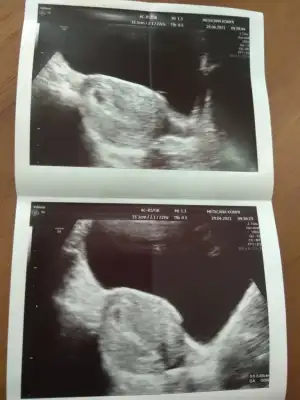

deneyimli hanımlar bu 10 haftalık bir gebelikte çift çizgi olurdu değil mi? iki kez regl oldum ama üstüne görmeden korkuyorum